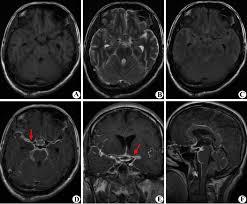

5.CT,MRI檢查,腦CT約半數顯示異常,炎性滲出物充填基底池及腦外側裂,部分患者腦實質內顯示結核瘤,直徑0.5~5cm,單發或多發,多位於額,顳及頂葉,增強掃描顯示環狀強化或密度增高。

腦MR採用Gd-DTPA增強,顯示基底池等部位強化,並較易發現腦實質內的結核瘤和小梗死灶。